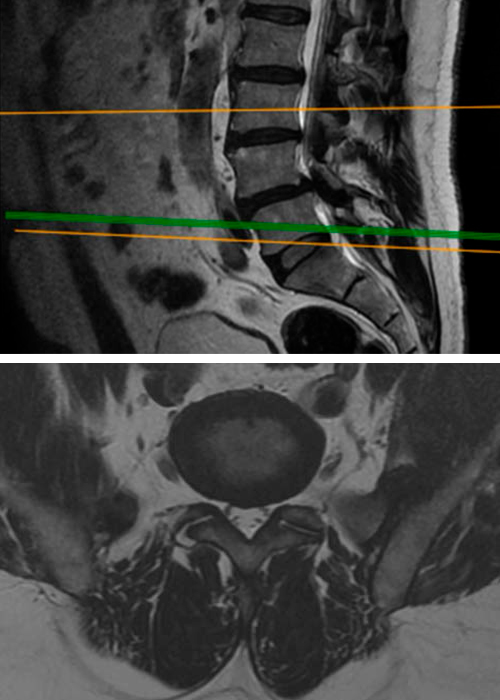

Paciente que acude a consulta, por un severo dolor en las piernas, impotencia funcional e incapacidad para la bipedestación prolongada.

Sufre calambres en ambos gemelos y dolor a partir de las cinco minutos de marcha que se siguen con parestesia en el tercer cuarto y quinto dedos del pie que imposibilita continuar la marcha.